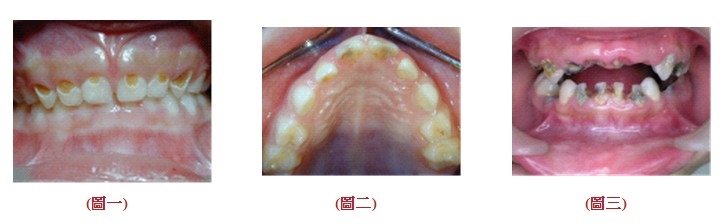

早發性齲齒可分三類:

1︰輕到中度︰乳門齒或乳臼齒有齲齒,但沒有嚴重到侵犯到唇舌側(圖一)

2︰中到重度︰上前乳門齒唇舌側均有齲齒(圖二)

3︰重度早發性幼兒齲齒︰齲齒已嚴重到,幾乎所有牙齒都侵犯包含乳下門齒(圖三)